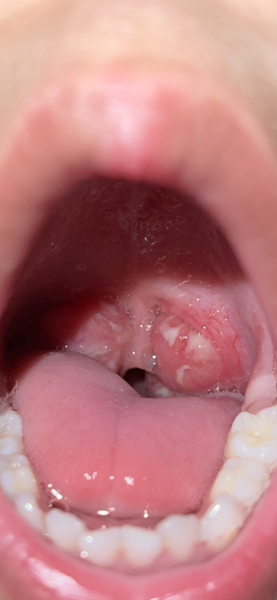

Tonsillitis pic

My Lo has enlarged tonsils, they have become inflamed again and the doctor has prescribed antibiotics. Normally they don’t have white on them but they do this time around. I’m very concerned, doctor didn’t see him but asked about symptoms and prescribed the medication over the phone. I’ve attached a photo, although I’ve read this is food/milk deposit but just want reassurance. Tia x